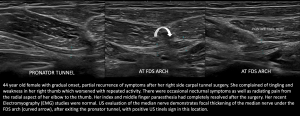

Fig 8: COMPRESSION AT THE PRONATOR TUNNEL - Compression at Flexor Digitorum Superficialis (FDS) Arch

Fig 9: COMPRESSION UNDER FDS ARCH - Charcot Marie Tooth Disease with superimposed Bilateral Double Crush Syndrome: Compression at Pronator Tunnel and Carpal Tunnel